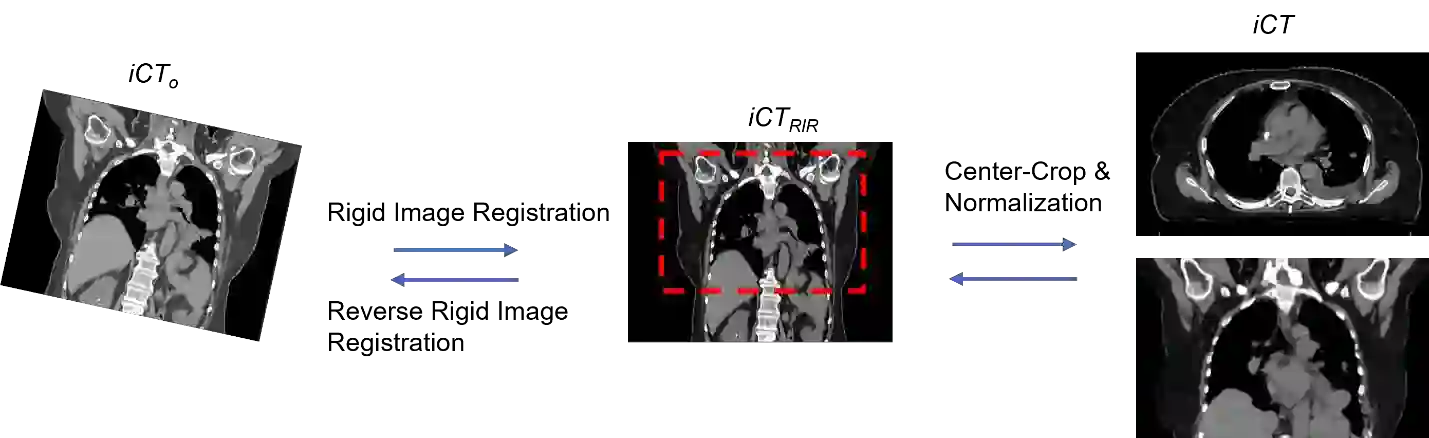

Purpose: In some proton therapy facilities, patient alignment relies on two 2D orthogonal kV images, taken at fixed, oblique angles, as no 3D on-the-bed imaging is available. The visibility of the tumor in kV images is limited since the patient's 3D anatomy is projected onto a 2D plane, especially when the tumor is behind high-density structures such as bones. This can lead to large patient setup errors. A solution is to reconstruct the 3D CT image from the kV images obtained at the treatment isocenter in the treatment position. Methods: An asymmetric autoencoder-like network built with vision-transformer blocks was developed. The data was collected from 1 head and neck patient: 2 orthogonal kV images (1024x1024 voxels), 1 3D CT with padding (512x512x512) acquired from the in-room CT-on-rails before kVs were taken and 2 digitally-reconstructed-radiograph (DRR) images (512x512) based on the CT. We resampled kV images every 8 voxels and DRR and CT every 4 voxels, thus formed a dataset consisting of 262,144 samples, in which the images have a dimension of 128 for each direction. In training, both kV and DRR images were utilized, and the encoder was encouraged to learn the jointed feature map from both kV and DRR images. In testing, only independent kV images were used. The full-size synthetic CT (sCT) was achieved by concatenating the sCTs generated by the model according to their spatial information. The image quality of the synthetic CT (sCT) was evaluated using mean absolute error (MAE) and per-voxel-absolute-CT-number-difference volume histogram (CDVH). Results: The model achieved a speed of 2.1s and a MAE of <40HU. The CDVH showed that <5% of the voxels had a per-voxel-absolute-CT-number-difference larger than 185 HU. Conclusion: A patient-specific vision-transformer-based network was developed and shown to be accurate and efficient to reconstruct 3D CT images from kV images.